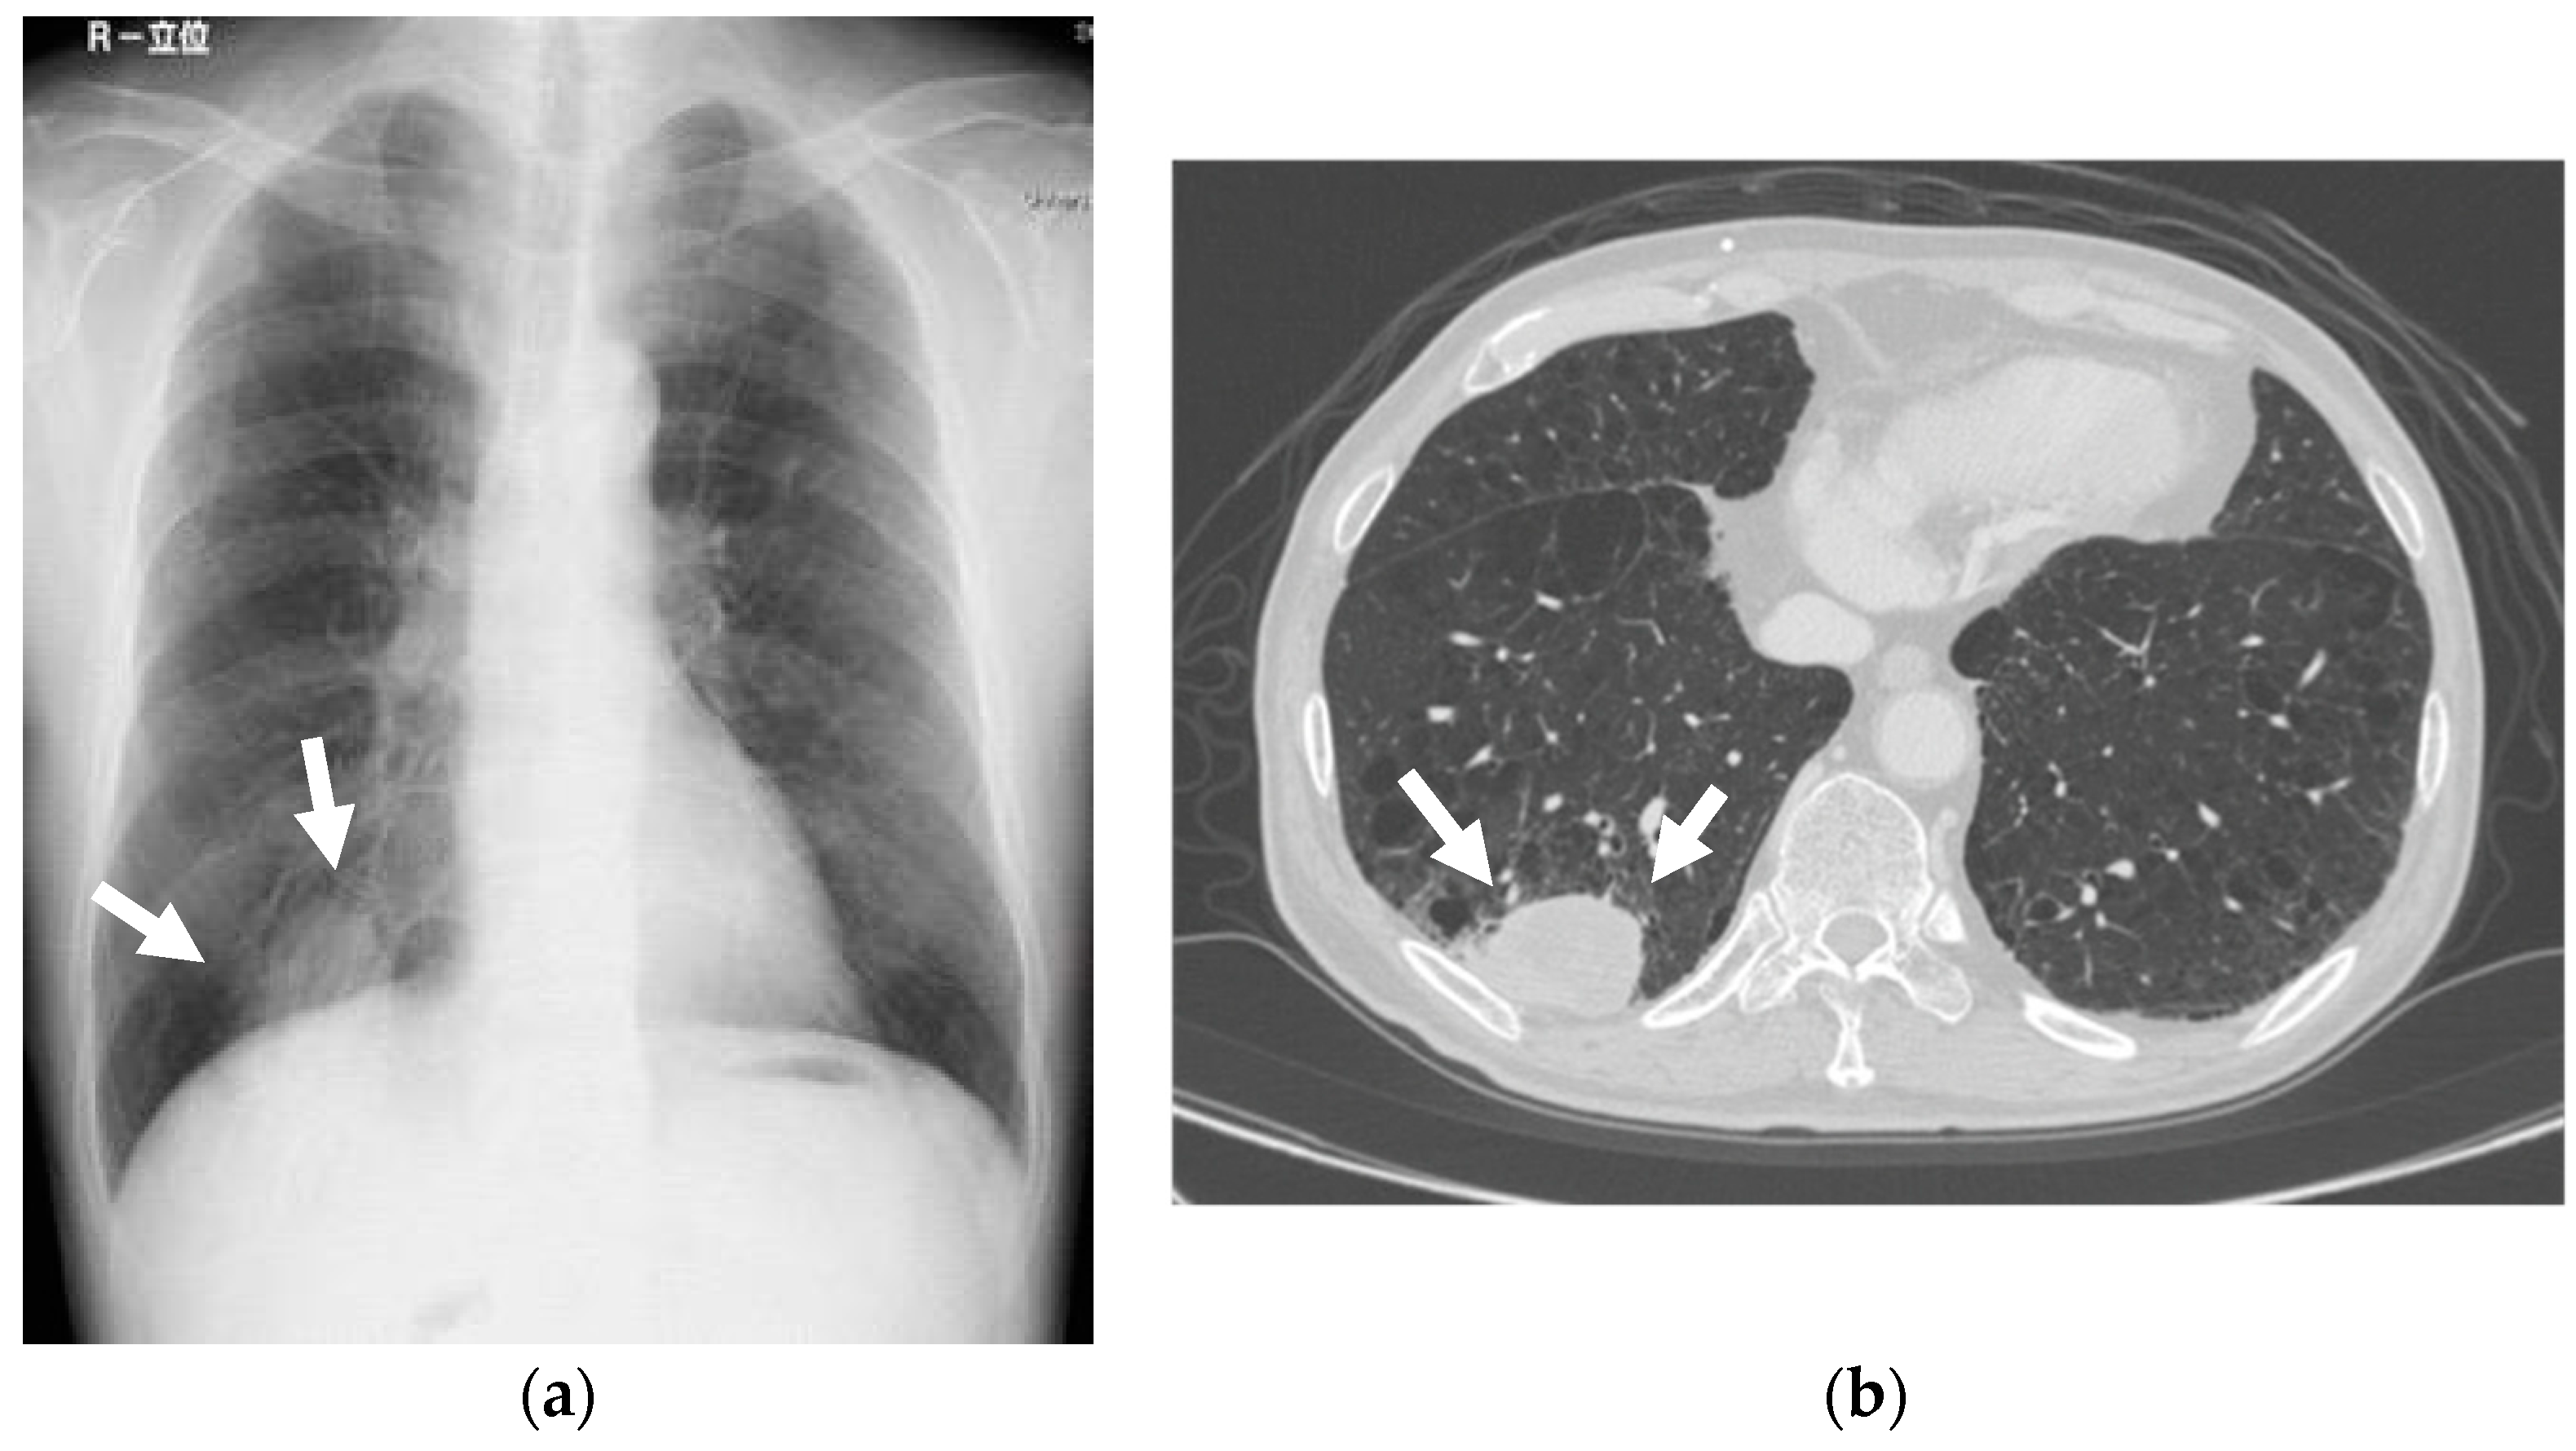

Figure 2.

Mass nodule. Chest X-rays revealed a 40 mm high-density mass nodule at the right lower lobe of the lung. The CT depicted a high-density mass in the right S10, measuring 60 × 35 mm. (a) Chest X-rays; (b) CT.